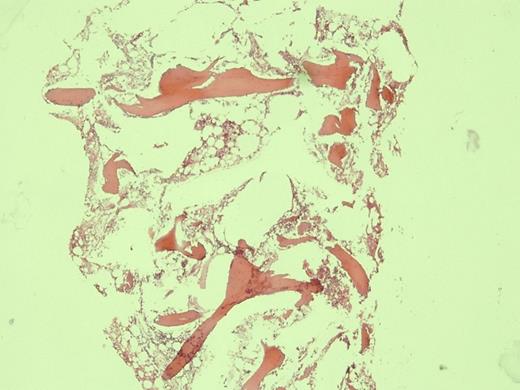

A previously healthy and normal family history 15 years old boy presented with epistaxis, pallor, jaundice, choluria and slightly hepato and splenomegaly, which were confirmed with full body CT scan, and no other alterations were detected. Remarkable results from AMA designated disease/organ panels were Hb 11.7 g/dL, adjusted reticulocytes 0.26%, neutrophils 0.931 K/µL, platelets 5.0 K/µL, ALT 1920 U/L, AST 2300 U/L, conjugated bilirubin 17 mg/dL, unconjugated bilirubin 15 md/dL, ferritin 1135 ng/mL. Supportive care was given and study for pancytopenia and hepatitis was started. Negative results from complete autoimmune panel including anti-LKM, anti-smooth muscle and anti-mitochondrial antibodies; panels for all hepatitis viruses, HIV, STORCH, EB, CMV, PVB19 and leptospira were negative. The patient was prepared for biopsies. Liver biopsy showed steatohepatitis, grade 2 fibrosis and lymphocyte infiltrates. Bone marrow biopsy showed 5% cellularity with absence of myeloid and megakaryocytes precursors, only erythroblasts and lymphoplasmocytoid cells; flow cytometry reported no abnormal cells and G-band karyotypes with and without mitomycin were normal. While the results from the biopsies the hepatic function improves but pancytopenia worsened to Hb 6.4 g/dL and neutrophils 0.124 K/µL. IHAAA was diagnosed and the patient continues with supportive care while results from siblings for allogeneic transplant arrive.